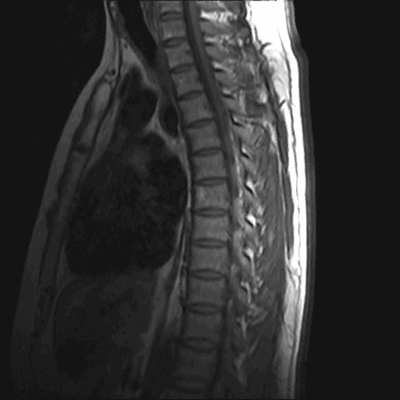

Множественные (2) гемангиомы на МРТ грудного отдела позвоночника

Гемангиомы на магнитно-резонансной томографии грудного отдела позвоночника (сагиттальная проекция, Т2 взвешенная последовательность)